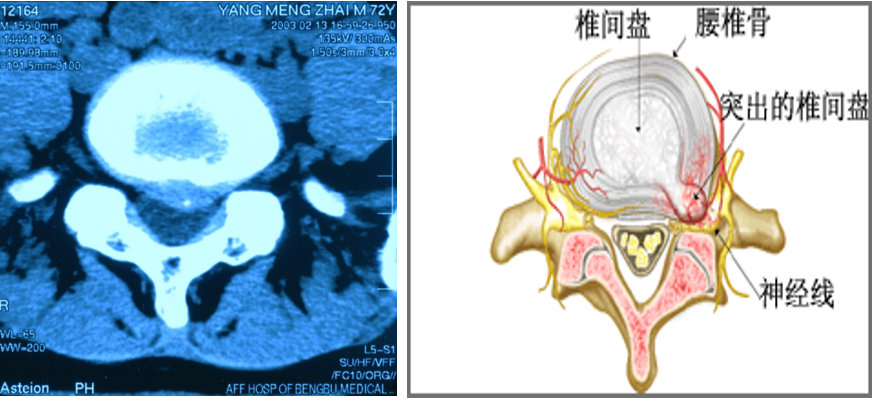

椎间盘突出症分类与微创方法的选择

1、椎间盘膨出(高压力):化学溶核类、机械减压类

2、椎间盘突出(高压力):机械减压类、化学溶核类、靶点治疗类、机械摘除类

3、椎间盘脱出 低压力:机械摘除类

4、椎间盘空洞 低压力:靶点治疗类、纤维环成形术